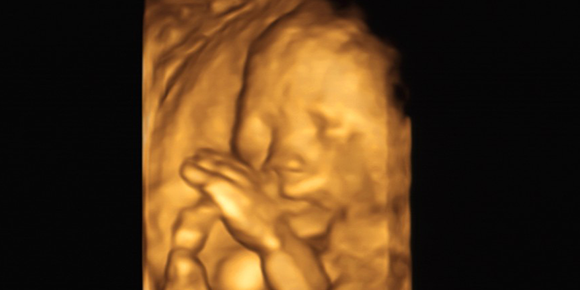

百佳是华东地区超声诊断培训基地;又和美国GE公司合作,技术不选新颖,只选成熟,画面清晰,让爸妈看到胎儿运动。